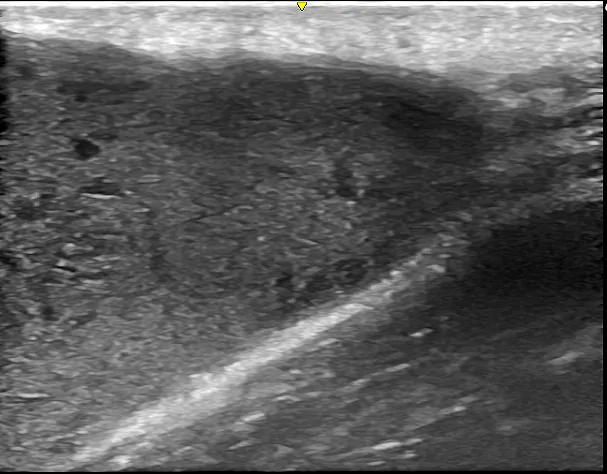

術後半年後には、わずかな変形は認められるものの、傷跡は目立たず、超音波検査で再発がないことを確認し、治療を終了しました。

術後半年後 ①